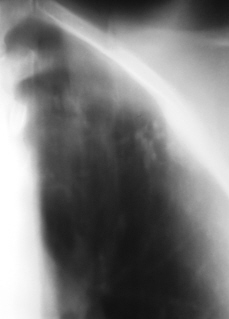

На фрагментах рентгенограмм (иллюстрации 3, 4), в прямой стандартной проекции слева под ключицей определяются полиморфные, различных размеров очаги.